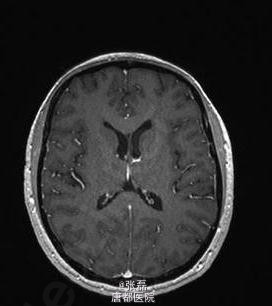

患者女性,46 岁,因头疼加重 2 周住院。住院时表现为颈部僵硬,伴有眩晕。头颅 MRI 未见明显异常。脑脊液结果示:中性粒细胞 133 个 /μl,嗜酸性粒细胞 38%。血清囊虫抗体滴度 106(正常≤0)。 脊髓 MRI 示:颈部单发囊性占位,腰部蛛网膜下腔多发囊性占位。故诊断为脊髓囊虫病,给予阿苯达唑 (2×400 mg/ 天) 驱虫、激素(强的松 60 mg/ 天)抗炎治疗 4 周。治疗期间,患者症状明显缓解,但是在随访 6 个月时,颈部疼痛仍未见缓解,MRI 示颈部囊性占位体积有所增大。